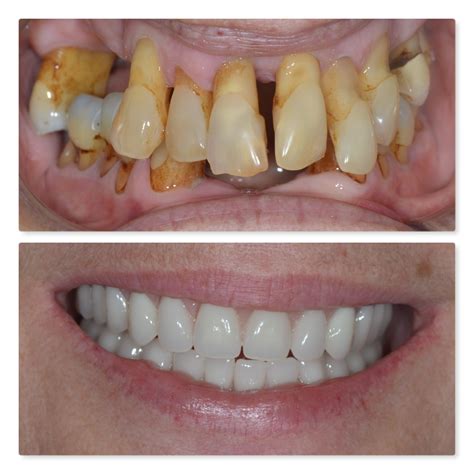

While severe bone loss often cannot be reversed, it can be stopped, and in some cases, the bone can be regenerated. The approach to treatment depends entirely on the severity of the condition and the underlying cause.

• Bone Grafting: This involves placing synthetic or natural bone material into the area of loss to encourage the body to grow new, healthy bone.